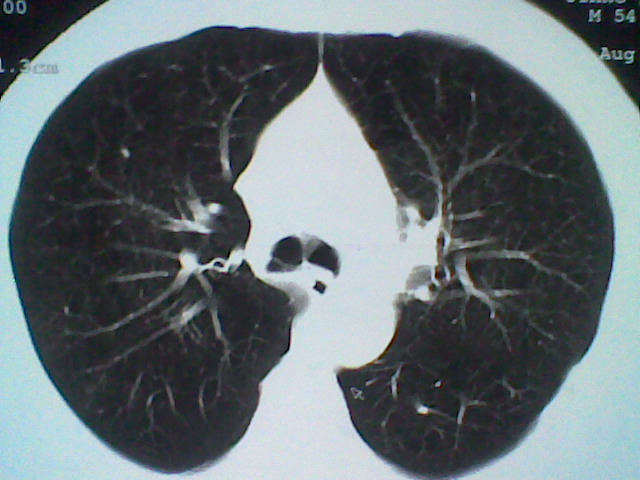

支扩伴感染。

支持 支气管扩张并感染。

支持楼主意见,考虑支气管扩张并感染。

支气管扩张并感染。